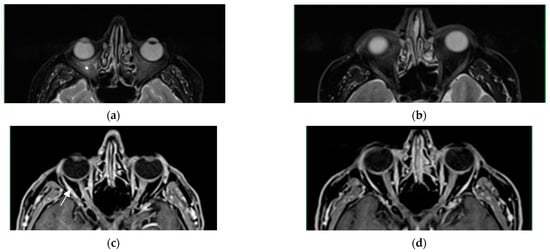

Figure 4.

T2-weighted images with fat saturation, axial plane—(a,b). Moderate edema of the intraconal fat secondary to optic neuritis ((a)—white asterisk). Resolution of edema on follow—up examination (b). T1-weighted image with gadolinium contrast administration, axial plane—(c,d). Heterogeneous optic nerve enhancement, more significant on the right side ((c)—white arrow). Marked partial regression of lesions on follow-up examination (d).